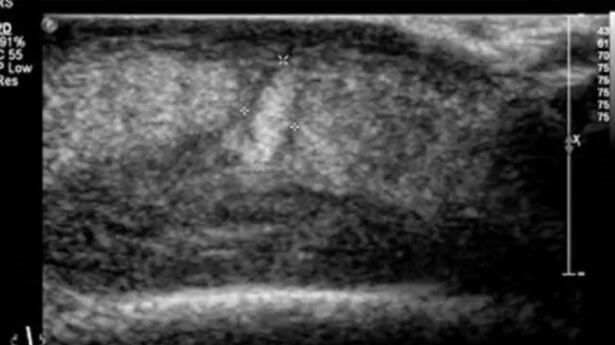

Vid en senare ultraljudsundersökning på kvinnans huvud, hittade man ännu mer larver inuti hennes huvud vilket ledde till en operation för att ta bort dessa insekter.